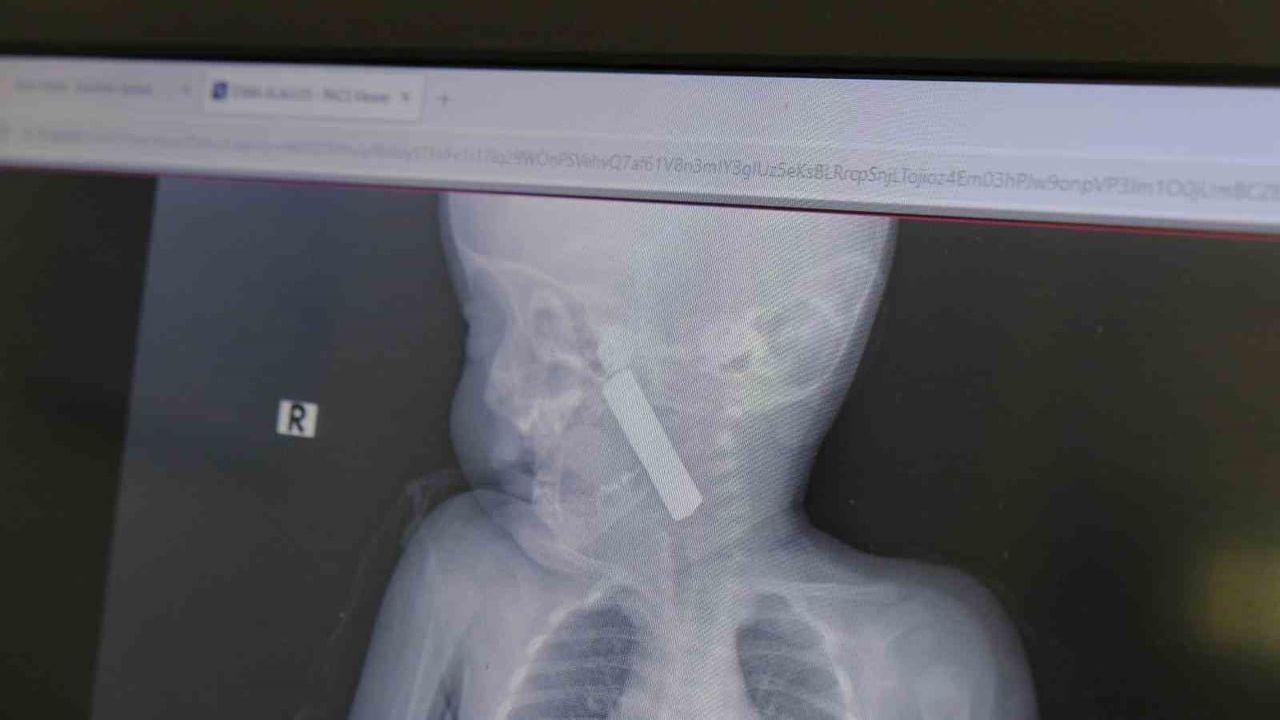

Karaman Eğitim ve Araştırma Hastanesi acil servisine kusma şikayetiyle getirilen 6 aylık E.A. isimli kız bebekte yapılan muayene ve tetkiklerde, boğazına kumanda pili kaçtığı tespit edildi.

Bebekte solunum sıkıntısı gözlenirken hastanın oksijen satürasyonu yaklaşık 90 civarındaydı ve siyanotik görünüm mevcuttu. Durumun ciddiyeti üzerine bebek vakit kaybetmeden ameliyata alındı.

Çocuk Cerrahisi Uzmanı Doç. Dr. Mehmet Uysal başkanlığındaki ekip tarafından yapılan operasyonda, anestezi ekiplerinin entübasyonunu takiben laringoskop ve magill forseps kullanılarak yabancı cisim çıkarıldı.

Doç. Dr. Mehmet Uysal olayla ilgili, "Acil polikliniğimize kusma şikayeti ile 6 aylık bir kız bebek getirilmiş ve bize haber verildi. Biz de vakit kaybetmeden geldik, hastamızı gördük. Yapılan tetkikler sonucunda, ağız tabanına oturan ve yemek borusunun birinci darlığına kadar uzanan, kumanda pili dediğimiz bir pille karşılaştık. Filmde ve muayenede bunu gördük. Hastayı ilk gördüğümüzde bayağı siyanotik durumda, solunum sıkıntılıydı ve oksijen satürasyonu 90 civarındaydı. Böyle olunca bir an önce beklemeden hızlı bir şekilde ameliyathaneye götürdük. Orada ameliyathanedeki anestezi uzmanlarımız ve personel bize yardımcı oldu, hasta hızlı bir şekilde entübe edildi. Ondan sonra da laringoskop ve magill forseps dediğimiz malzemelerimizle bu yabancı cismi çıkarmış olduk. Bir an evvel müdahale ettik, iyi ki müdahale ettik, orada ağız tabanında, özellikle ön kısmında hasar oluşmuştu. Müdahale sonrasında da hastanın solunum problemleri bir süre devam etti, bu yüzden 24 saat takip ettik. Herhangi bir problem oluşmayınca 24 saat sonra kontrole gelmek üzere hastayı taburcu ettik," dedi.